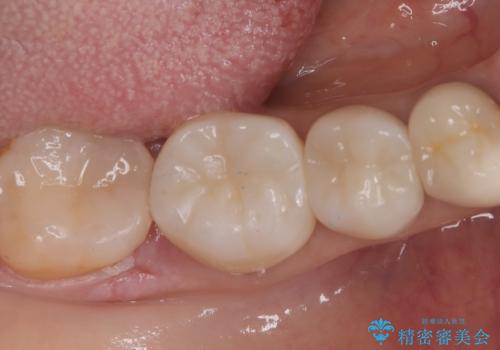

【セラミックインレー】笑うと銀の詰め物が目立つ

右下7番目の歯に保険適用のメタルインレーが入っており、大きなう蝕などは認めなかったため概形は大きく変えずセラミックインレーへやり替えとなりました。

やり替える過程で古い裏層材やカリエスは全て除去し、新たにCR裏層を行っています。

セラミックインレーセット時はラバーダム防湿を行っています。